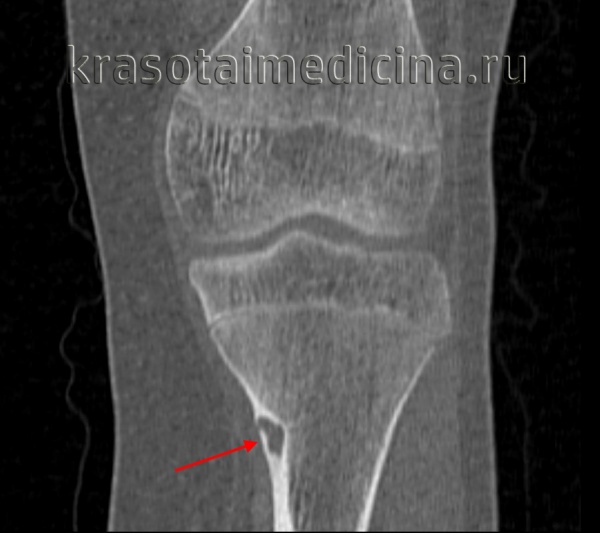

- Рентгенография кости. На снимках визуализируется кистообразные изменения или неоплазия в виде «мыльных пузырей» в метафизарной зоне. Признаки общего остеопороза отсутствуют, вокруг измененного участка может просматриваться остеосклероз. Границы доброкачественной ГКО более четкие, но из-за местно-агрессивного роста при значительном размере возможно появление «костного козырька». Выраженная периостальная реакция нехарактерна. Злокачественная остеокластома имеет нечеткую структуру. На снимках рано обнаруживается разрушение кортикального слоя.

- КТ и МРТ кости. Компьютерная томография дает более четкое представление о форме, размерах, границах гигантоклеточной опухоли, в сомнительных случаях позволяет подтвердить или опровергнуть разрыв коркового слоя. В ходе магнитно-резонансной томографии исследуют интрамедуллярный и кистозный компоненты, оценивают состояние окружающих мягких тканей, расположение сосудов и нервов. Методики помогают выбрать оптимальный вариант хирургического вмешательства, спланировать операцию.

КТ таза. Метастатическая карцинома подвздошной кости слева с деструкцией костной ткани (красная стрелка) и обширным мягкоктанным компонентом (зеленая стрелка)